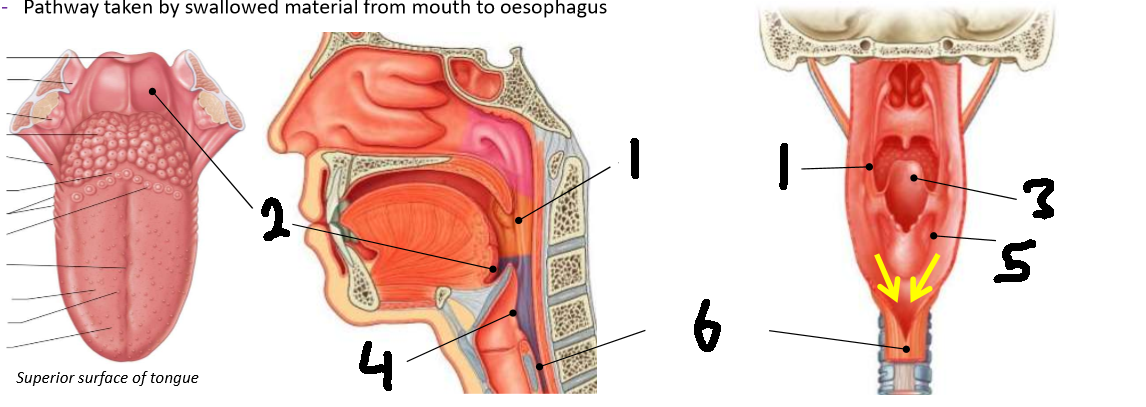

What is 1?

palatopharyngeal arch

What is 2?

vallecula

What is 3?

epiglottis

What is 4?

laryngeal inlet

What is 5?

piriform fossa

What is 6?

oesophagus